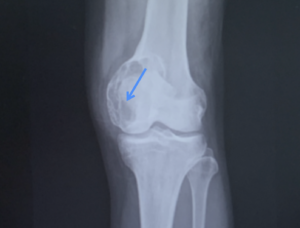

診断はX線が簡便かつ有効ですね。

骨端に及ぶ腫瘍は多くないですが、

”骨巨細胞腫”は骨幹端から骨端に偏心性、膨張性の病変です(下図の如く、イメージですが)

骨溶骨性病変を広範に認めますね。(透けて見える感じ)

辺縁は比較的明瞭で骨硬化を伴う例は少ないです。

進展例は内膜側からの侵食、外膜側の反応性骨形成での膨隆を認め、腫瘍内部に隔壁が存在するようにみえます。

soap-bubble-apperance

と聞けば、懐かしいと思う方いるんじゃないでしょうか。

これを見たら骨巨細胞腫を疑いましょう。